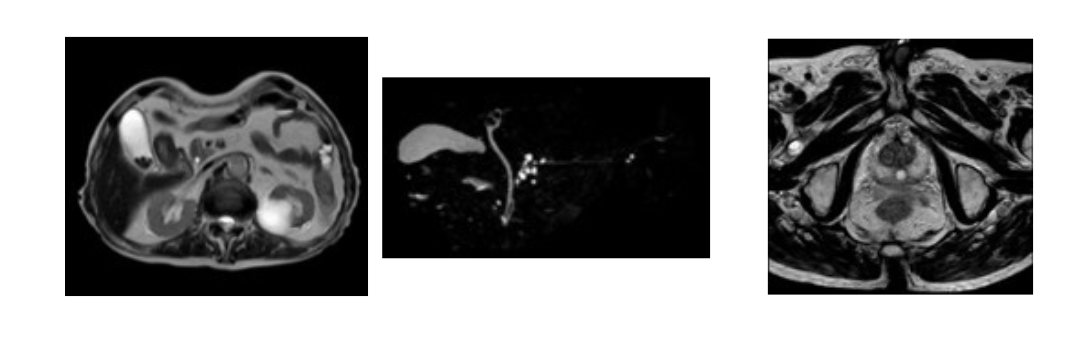

MRI検査

MRI(Magnetic Resonance Imaging、磁気共鳴画像法)は、磁石が埋め込まれたトンネルの中に体を入れて電波を使い、コンピューターにより体の中を映し出す検査です。X線被ばくはありません。

患者さん自身の体の位置を変えずに、あらゆる角度から体の中の様子をみることができます。

PHILIPS社製 Ingenia Prodiva 1.5T MRI装置(2022年3月から稼動)

【脳】 【脳血管】 【頸椎】

【腹部】 【前立腺】